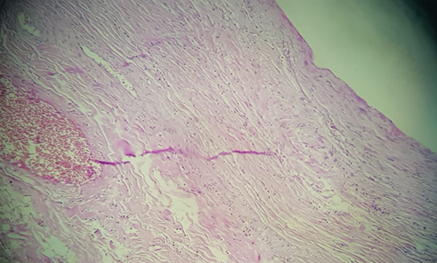

Figure 3 Histological section showing fusiform cells arranged in short bundles, with some histiocytes. Laterally, the lesion infiltrates thick dermal collagen. There are no nuclear atypies. No atypical changes in nucleus.